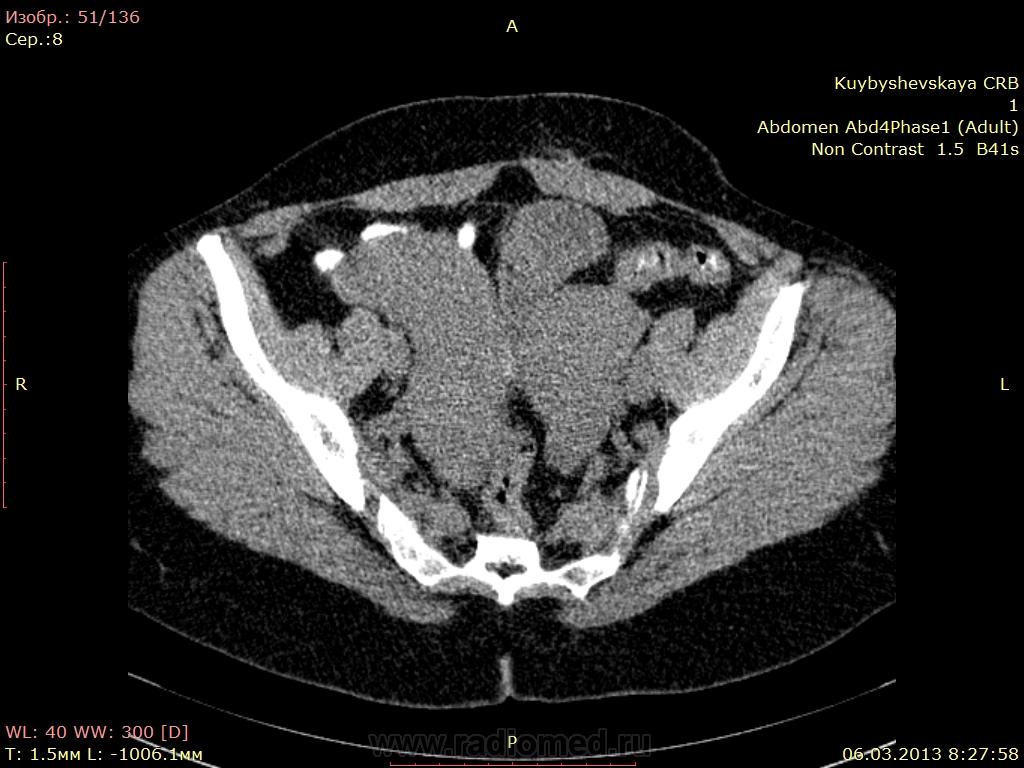

Здравствуйте. поступила к нам женщина 1970 г.р. по УЗИ Справа выше дна матки и кзади образование неправильной формы с четкими неровными контурами 11х7х10 неоднородное. правый придаток матки? правый яичник не лоцируется. левый 3,7х2,8х2,5

натив

учитывая ,что участок больше всего копит контраст в отсроченную фазу -то получается фибромиома

Скачала дайком. Спереди "на ножке", судя по сосудам, правый яичник. Здоровая ерундовина справа от матки - 2 варианта: либо опухоль широкой связки, либо буква З в схеме (атрезия правого рога, и нечто в нем). Резать, резать к чертовой матери, не дожидаясь перитонита! (с)